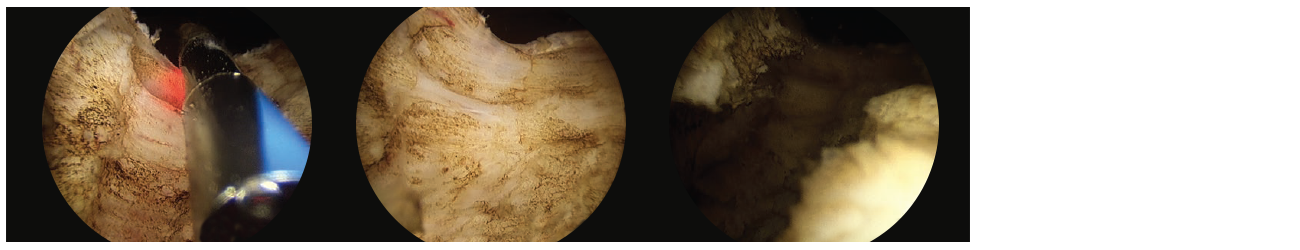

• Thereafter, I create deepened and widened groves from the bladder neck to the verumontanum at the 5 o’clock and 7 o’clock positions. (Fig. 2)

3 scope images. Identifying how to vaporize a working space. Figure 2: Groove creation at 7 o’clock down to capsule.